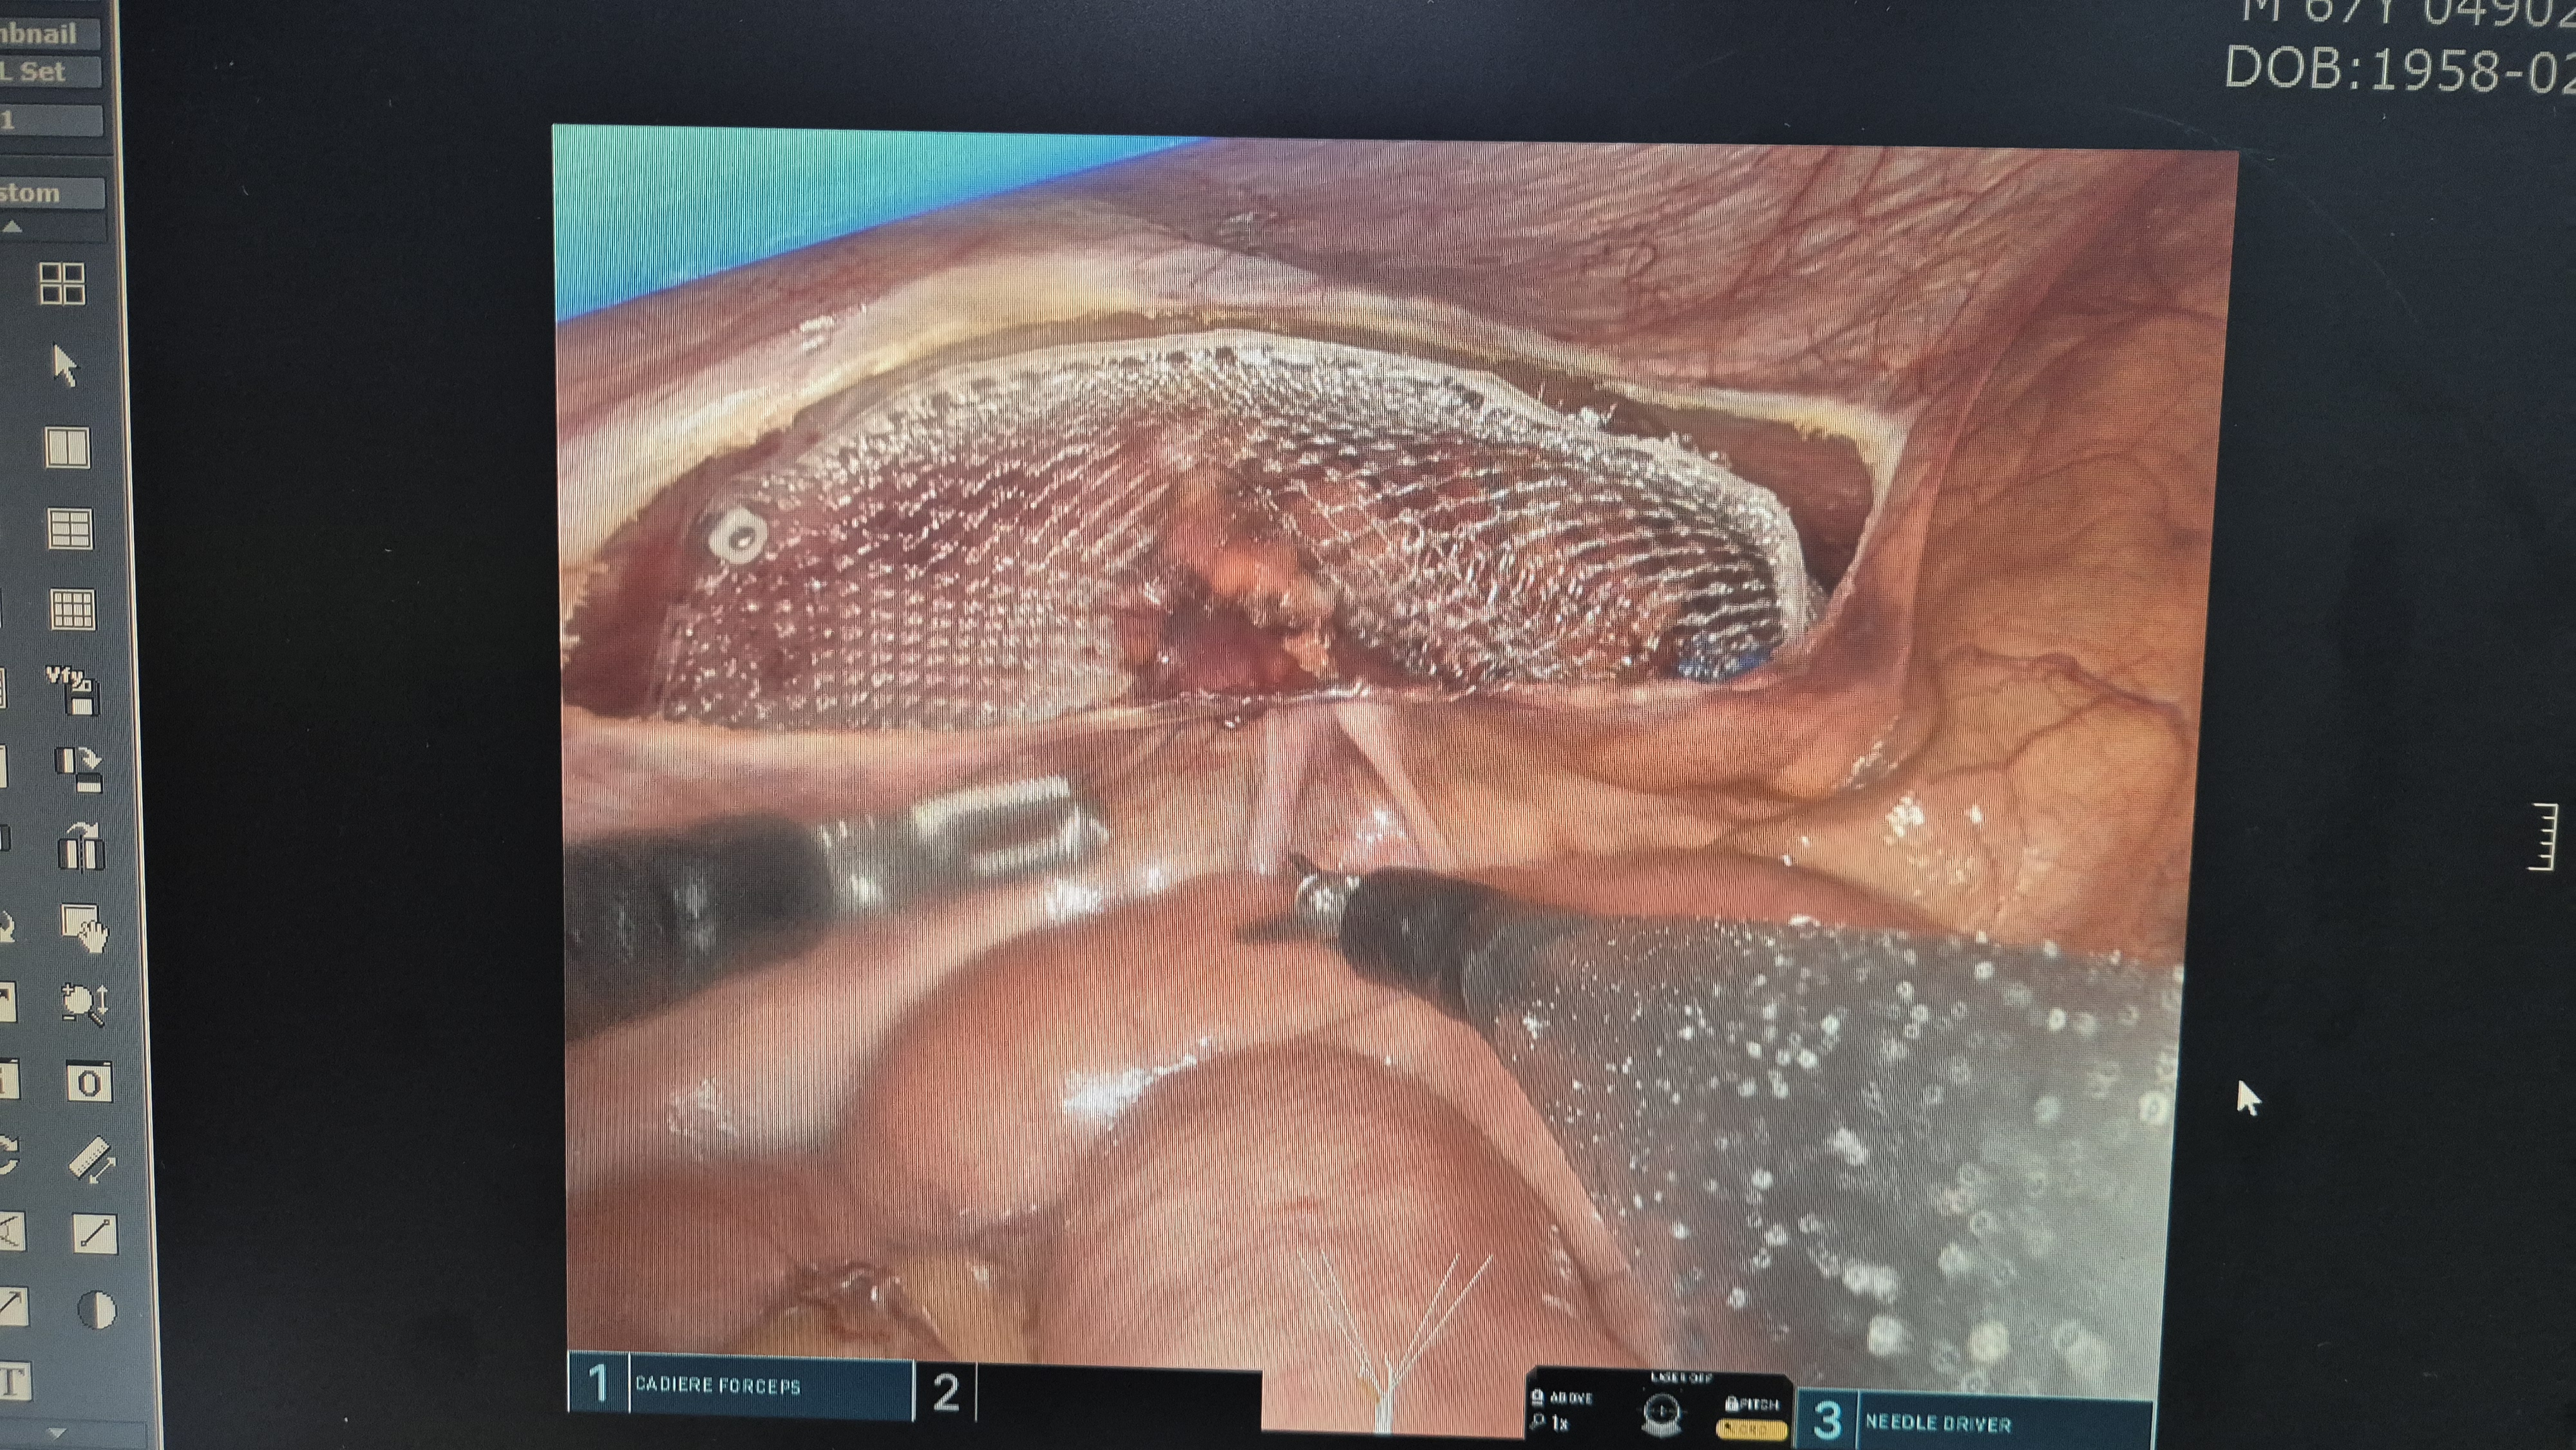

메쉬로 고정.